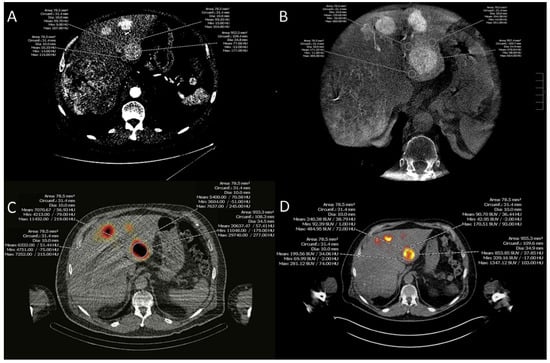

2.2. Image Acquisition

2.2.1. MDCT

2.2.2. CACT

2.2.3. SPECT/CT

2.2.4. PET/CT